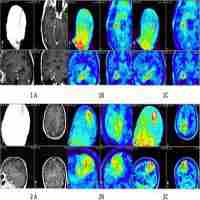

| Abstract | Neuroimaging based on O-(2-[18F]fluoroethyl)-L-tyrosine (FET)-PET provides additional information on tumor grade and extent compared to MRI. Dynamic PET for biopsy target selection further improves results but is often clinically impractical. Static FET-PET performed at two time-points may be a good compromise, but data on this approach are limited. The aim of this study was to compare the histology of lesions obtained from two challenging glioma patients with targets selected based on hybrid dual time-point FET-PET/MRI. Five neuronavigated tumor biopsies were performed in two difficult cases of suspected glioma. Lesions with (T1-CE) and without contrast enhancement (T1 and T2-FLAIR) on MRI were selected. Dual time-point FET-PET imaging was performed 5-15 minutes (PET10) and 45-60 minutes (PET60) after radionuclide injection. The most informative FET-PET/MRI images were co-registered with MRI in time of biopsy planning. Five biopsy targets (three from high uptake and two from moderate uptake FET areas) thought to represent the most malignant sites and tumor extent were selected. Histopathological findings were compared with FET-PET and MRI images. Increased FET uptake in the area of non-CE locations on MRI correlated well with high grade gliomas localized as far as 3 cm from T1-CE foci. Selecting a target in the motor cortex based on FET kinetics defined by dual time-point PET resulted in a grade IV diagnosis after previous negative biopsies based on MRI. An additional grade III diagnosis was obtained from an area of glioma infiltration with moderate FET uptake (between 1-1.25 SUV). This findings seem to show that dual time-point FET-PET-based biopsies can provide additional and clinically useful information for glioma diagnosis. Selection of targets based on dual time-point images may be useful for determining the most malignant tumor areas and may therefore be useful for resection and radiotherapy planning. |